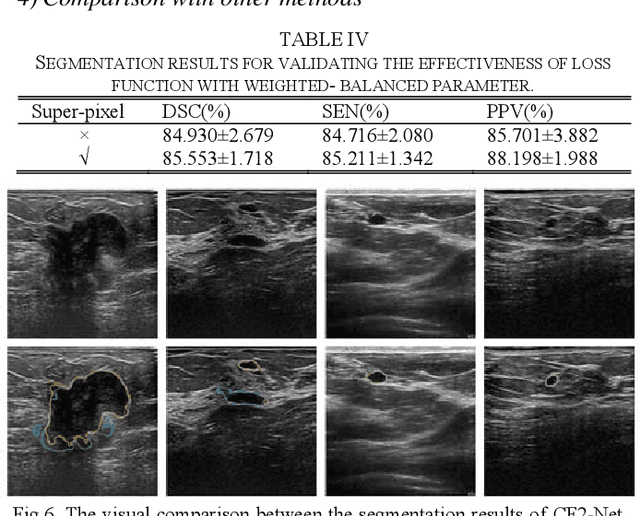

Abstract:Breast ultrasound (BUS) image segmentation plays a crucial role in a computer-aided diagnosis system, which is regarded as a useful tool to help increase the accuracy of breast cancer diagnosis. Recently, many deep learning methods have been developed for segmentation of BUS image and show some advantages compared with conventional region-, model-, and traditional learning-based methods. However, previous deep learning methods typically use skip-connection to concatenate the encoder and decoder, which might not make full fusion of coarse-to-fine features from encoder and decoder. Since the structure and edge of lesion in BUS image are common blurred, these would make it difficult to learn the discriminant information of structure and edge, and reduce the performance. To this end, we propose and evaluate a coarse-to-fine fusion convolutional network (CF2-Net) based on a novel feature integration strategy (forming an 'E'-like type) for BUS image segmentation. To enhance contour and provide structural information, we concatenate a super-pixel image and the original image as the input of CF2-Net. Meanwhile, to highlight the differences in the lesion regions with variable sizes and relieve the imbalance issue, we further design a weighted-balanced loss function to train the CF2-Net effectively. The proposed CF2-Net was evaluated on an open dataset by using four-fold cross validation. The results of the experiment demonstrate that the CF2-Net obtains state-of-the-art performance when compared with other deep learning-based methods